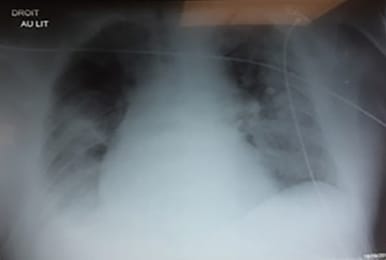

L'échographie pulmonaire peut-elle orienter le choix du traitement en kinésithérapie respiratoire ?